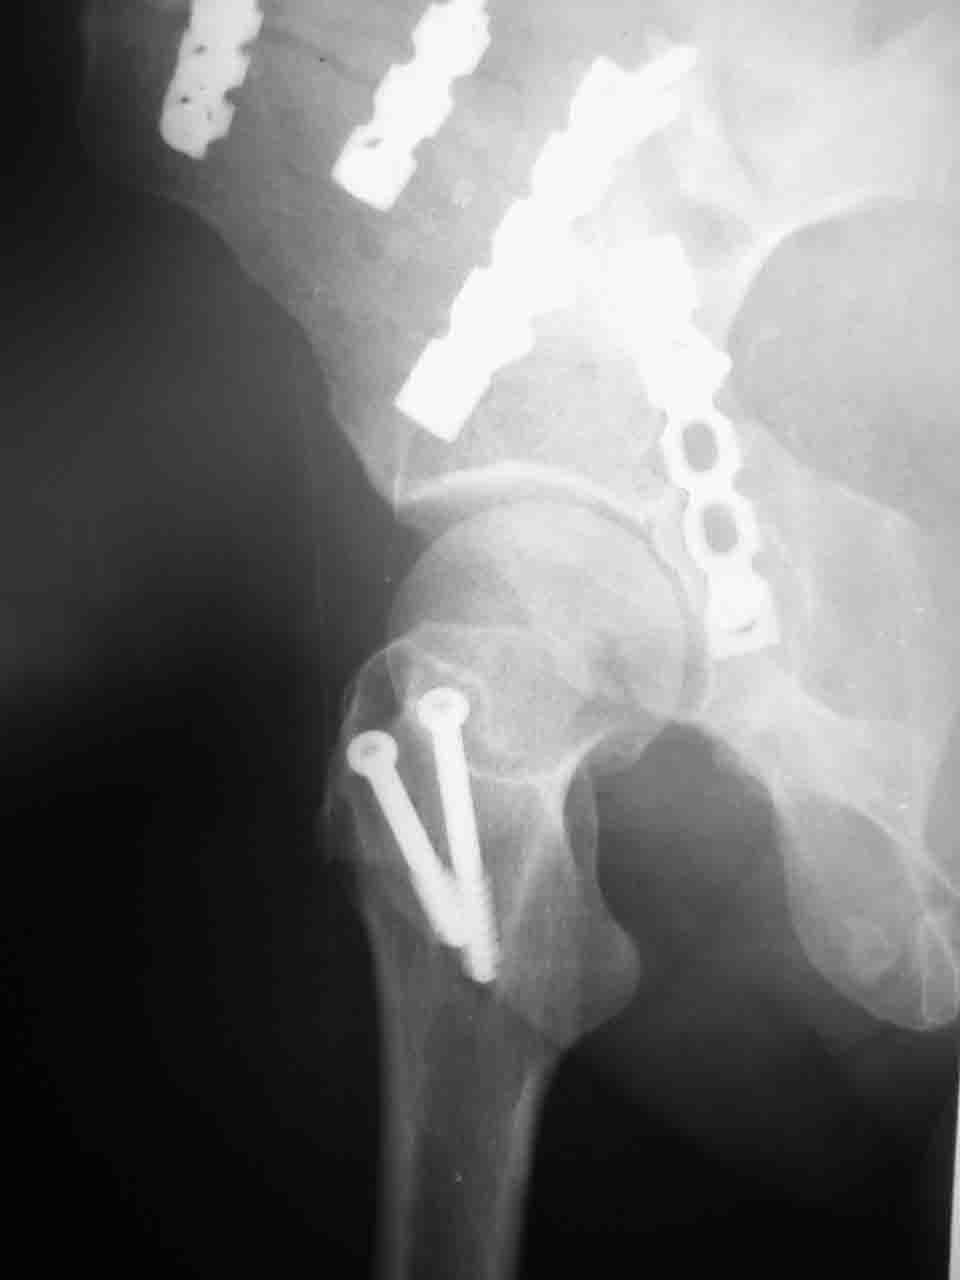

Вопрос доступа к вертлужной впадине при остеосинтезе задача не простая. Конечно, у Летурнеля и Тайла всё давно описано, нам остается только брать на вооружение. Но сами понимаете, что не бывает двух одинаковых ситуаций, поэтому в каждом случае вопрос решается сугубо индивидуально. Наша главная цель - восстановить анатомию с нанесением минимальной дополнительной травмы тазобедреннному суставу, думаю с этим никто не поспорит. Расширенный илиофеморальный доступ уж слишком травматичен (как сказал один коллега "таз лежит отдельно, больной отдельно").Стоит ли делать из пациента анатомический препарат для того чтобы легче ориентироваться. Да и нужно ли собирать всю "мозаику"? Мы применяли при таких операциях своеобразную операционную хитрость - сначала устраняли грубое смещение крыла под гребнем с фиксацией так называемой "плавающей" пластиной (временно фиксированной на двух винтах)- доступ или продлевали боковой, или делали небольшой дополнительный разрез над гребнем. Это позволяло устранить грубое смещение и захождение отломков тела повздошной кости, что значительно облегчало репозицию и остеосинтез впадины над сводом. Основное внимание конечно же уделяли нагружаемому задне-верхнему отделу. Сообщите ваш адрес, пришлю схемы и рентгенограммы.